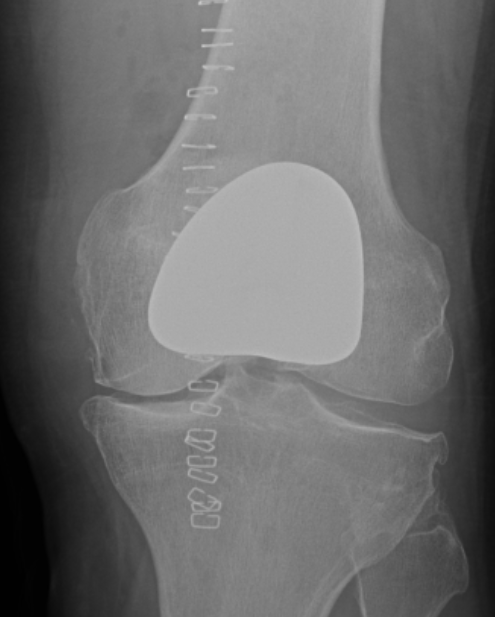

Patellofemoral joint replacement

Technique